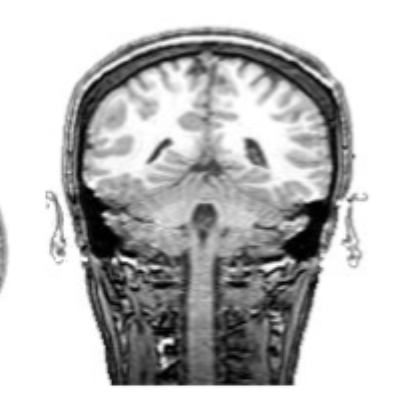

what slice of brain is this?

coronal slice